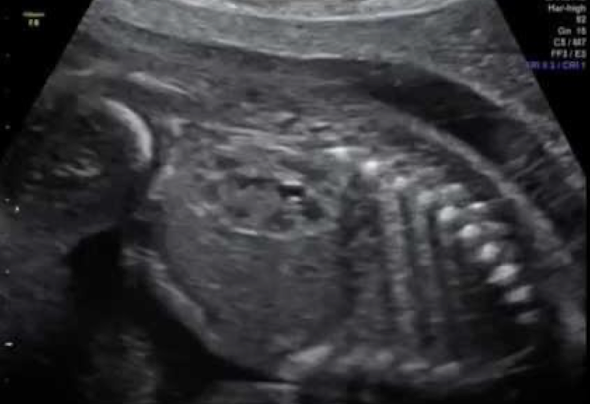

what plane was this taken in?

transverse